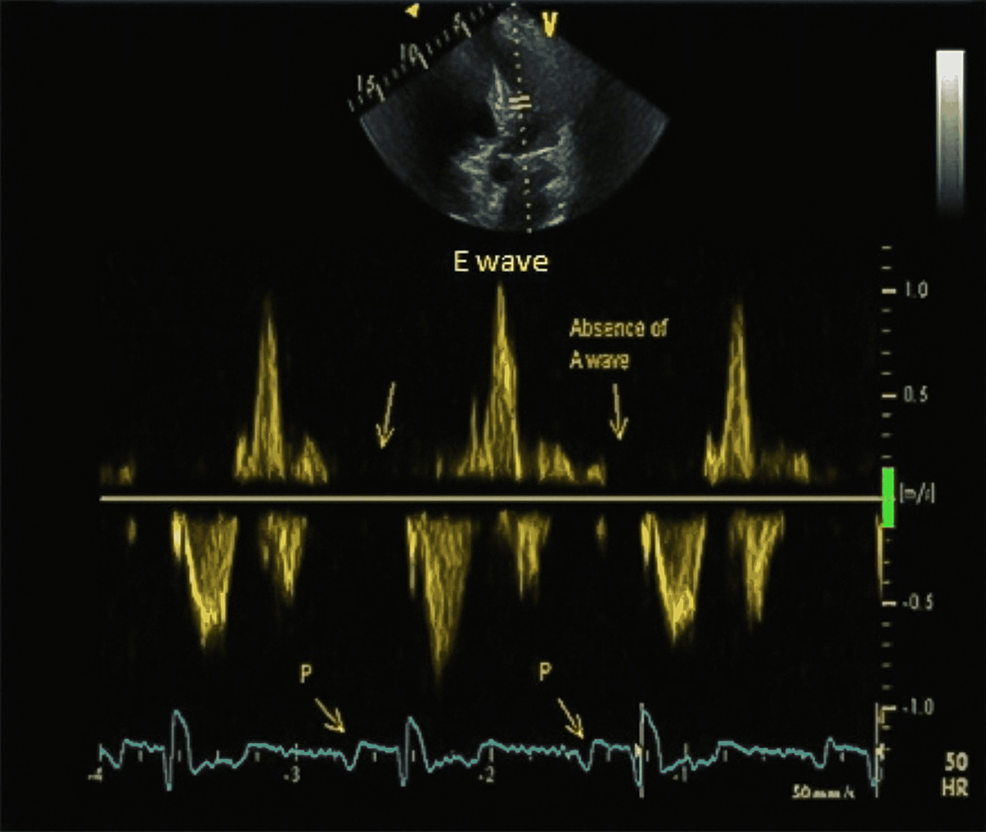

Cureus Persistent Atrium Standstill Post Atrial Fibrillation Ablation

Cureus Persistent Atrium Standstill Post Atrial Fibrillation Ablation Standstill Disease It is well documented that some patients with a. Atrial standstill is a rare cardiac rhythm disease with a few familial and sporadic cases described to date that is characterized by a transient or permanent. The term sinoatrial disease is used interchangeably with sick sinus syndrome and describes a series of abnormalities that can result in profound sinus bradycardia, sinus. Standstill Disease.

Cureus Persistent Atrium Standstill Post Atrial Fibrillation Ablation Standstill Disease Atrial standstill is a rare condition in which the atrium loses its mechanical contraction with or without losing the electrical conduction. It is well documented that some patients with a. The term sinoatrial disease is used interchangeably with sick sinus syndrome and describes a series of abnormalities that can result in profound sinus bradycardia, sinus pauses, sinus arrest, sinoatrial nodal. Standstill Disease.